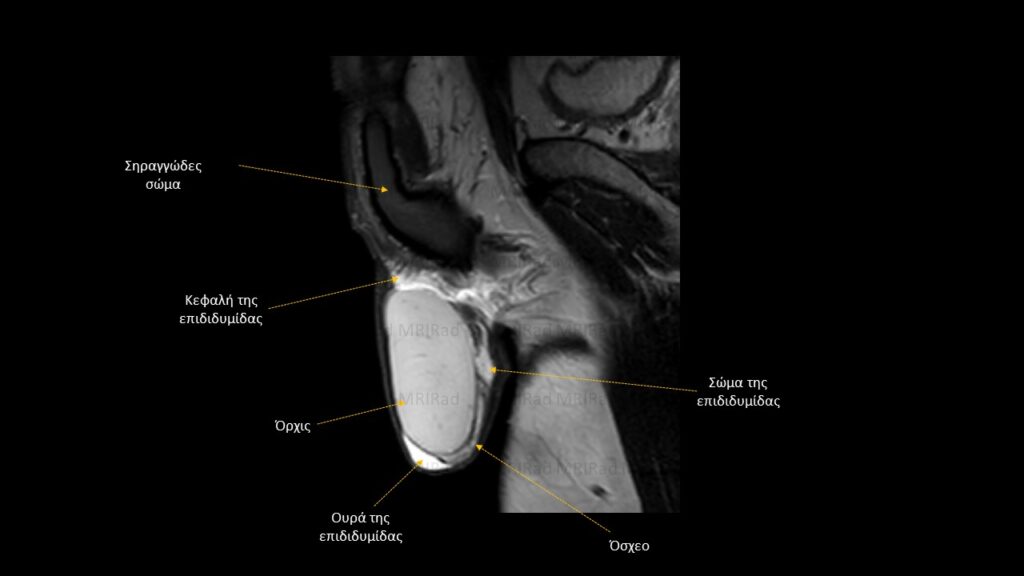

Βασική Ακτινοανατομία MRI Οσχέου